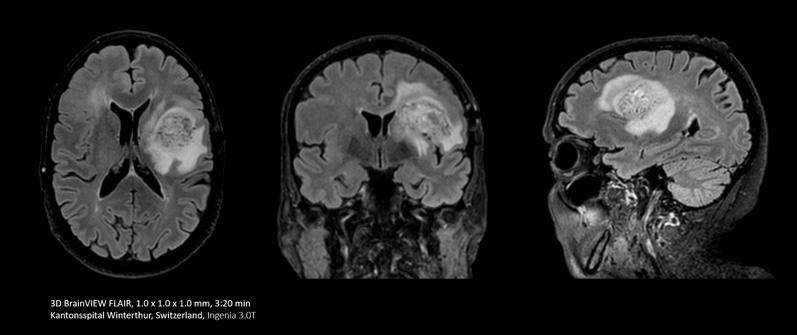

In some cases, like brain and spine examinations, it can be useful to use the power of Compressed SENSE to trade 2D MRI scan sequences for faster 3D sequences. This can allow clinicians to achieve high spatial resolution in tiny nerves and vessels.

Replace Sequences scan

With Compressed SENSE you can replace your single orientation 2D FLAIR scan with a multi-orientation 3D volumetric FLAIR scan in only 3 and a half minutes scan time.

I do a lot of brain imaging, and we used to do the FLAIR sequence using a 5 mm thick slice. Now with Compressed SENSE we are able to take a 3D volumetric scan for about 6 minutes down to maybe 3 and a half minutes.”

Dr. Mark Oswood, MD, PhD, Neuroradiologist, Hennepin Healthcare, Minneapolis, USA